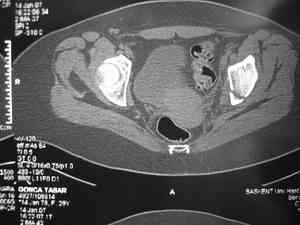

Обследование дополнительными снимками: прямая, инлет и оутлет, а КТ срезы покажет имевшиеся мозольные перемычки и истинное смещение в крестцово подвздошном сочленении.

Дорогой Андрей. Мы имеем дело с комбинированной (ротационно и вертикально) нестабильностью таза со смещением правого гнемипелвиса. При таких переломах, фиксация только переднего полукольца вне зависимости от метода фиксации, как уже было сказано Djoldas Kuldjanov, M.D., не может создать адекватной фиксации. И перелом пластины был вполне ожидаемым после активизации пациента. Смещение сохраняется, и по-видимому не 2 см., а все 4, если не более. Разница всего (+2 см) по конечностям как вы указываете, скорее скомпенсировано позвоночником и протезом. Дополнительные снимки или КТ исследование помогли бы уточнить степень смещения с точностью до мм., выявить перелом поперечного отростка пятого поясничного позвонка, или помимо разрыва правого крестцово-подвздошного сочленения выявить перелом боковой массы крестца справа и т.д. При возможности, конечно, все это желательно сделать. Но мало что изменится с практической точки зрения, т.к. задача - это низведение репозиция и надежная фиксация правого гемипелвиса. Учитывая плачевный опыт стержневого аппарата, давность травмы совершенно очевидно, что поставленная задача достижима при открытой репозиции и одномоментной фиксации переднего полукольца с артродезированием правого крестцово-подвздошного сустава. Операция выполняется в положении больного на здоровом боку или полубоку из расширенного трансоссального подвздошно-пахового доступа с переходом на лонное сочленение доступом по Pfannenstiel. Указанный доступ обеспечивает подход к крестцово-подвздошному сочленению как спереди так и сзади. После артродезирования выполняется синтез лонного сочленения. Клинический пример

Пациентка С.26 лет. Травма за 6 месяцев до поступления

Укорочение правой нижней конечности до 10см